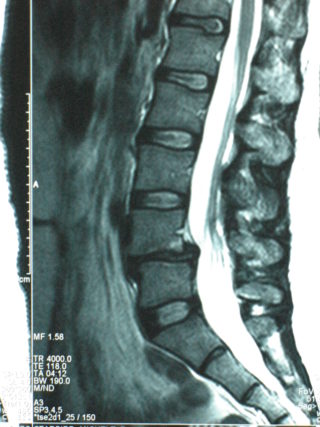

Sagittal MRI Spondylolithesis